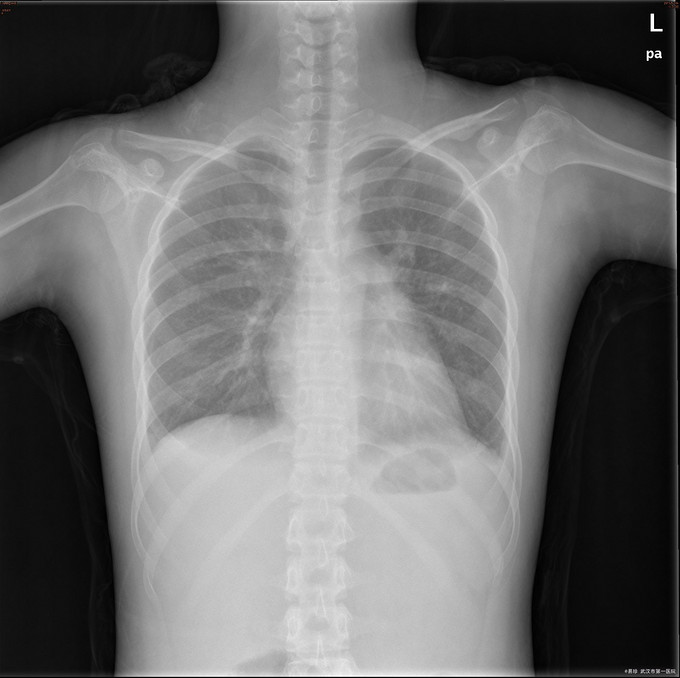

查体:T:38.5℃ P:102次/分 R:29次/分 BP:156/96mmHg 鼻部皮肤见散在淡红色皮疹,双小腿皮肤见色素沉着,未见皮疹、瘀斑。右颌下扪及一黄豆大小淋巴结,活动可,无压痛,质中,余浅表淋巴结未触及肿大。脸部淡红色碟形红斑,心肺听诊未闻及异常,腹软,无压痛及反跳痛,双下肢无浮肿。 辅查: 1.HGB85g/L、尿蛋白2+、尿潜血3+,血白蛋白22.9g/L、补体C3 0.09g/L、补体C4 0.02g/L,血肌酐151umol/l,Coombs试验阳性,ANA滴度1:3200,dsDNA阳性” 2.骨髓涂片提示:骨髓增生活跃,粒、红系比例正常,铁染色示缺铁,建议做铁蛋白检查。 3.胸片提示双下肺炎症。

诊断:1、I型呼吸衰竭;2、急性左心衰;3、咯血查因:狼疮性肺炎可能;4、肺部感染;5、系统性红斑狼疮,狼疮性肾炎,急性肾损伤,狼疮血液系统损害,狼疮心脏损害 左房左室增大 二尖瓣关闭不全(轻度) 三尖瓣关闭不全(轻度)心包积液 心功能Ⅲ级 治疗:入院后予以甲强龙、丙球抑制免疫反应,持续血透、抗感染、降压、面罩吸氧等治疗。但患者仍出现进行性血压升高、呼吸循环功能衰竭。后家属强烈要求出院并回当地治疗。